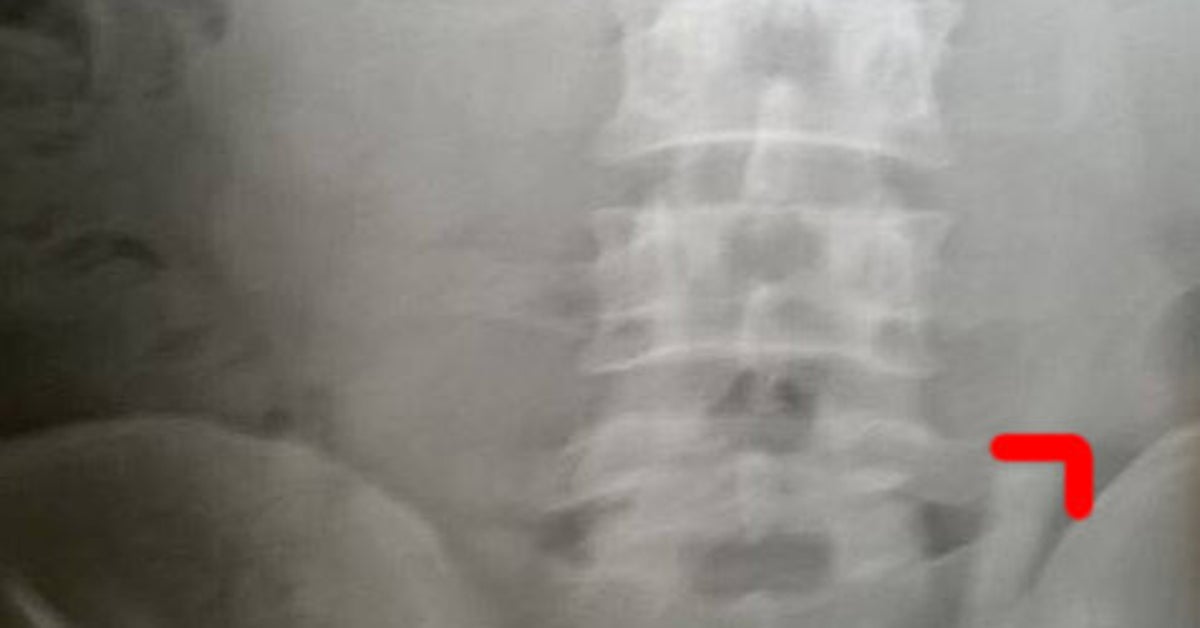

Definizione La perforazione gastrointestinale è una gravissima complicazione che tende a presentarsi all'improvviso e in modo drammatico, con un forte dolore addominale seguito dai segni dello shock. Parte terminale dell’intestino (fine del colon e retto), apparato riproduttore, nella donna l’utero, le tube, le ovaie e la vagina, nell’uomo la prostata, i dotti deferenti e le vescichette seminali Cause La causa più frequente delle aderenze addominali sono gli interventi chirurgici. Conseguenze della perforazione dell'intestino In caso di perforazione, l’ intervento immediato è fondamentale se l’intestino viene perforato, il suo contenuto può fuoriuscire nella cavità dello stomaco e causare peritonite (un’infezione delle viscere causata da contaminazione batterica).

Poiché la perforazione dell’intestino tenue o dell’intestino crasso spesso si verifica in corso di un’altra condizione dolorosa e dal momento che il contenuto che ne fuoriesce è talvolta contenuto in una piccola area della cavità addominale, senza ulteriore diffusione, i sintomi possono risultare meno gravi ed essere confusi per un’esacerbazione del problema originale. Pancia gonfia, dolori addominali, stipsi, colite sono tra i disturbi più comuni e diffusi al giorno d’oggi Ma perché questi fastidi sono così frequenti?. Peritonite secondaria (per invasione batterica o azione di agenti chimici a partenza da un focolaio.